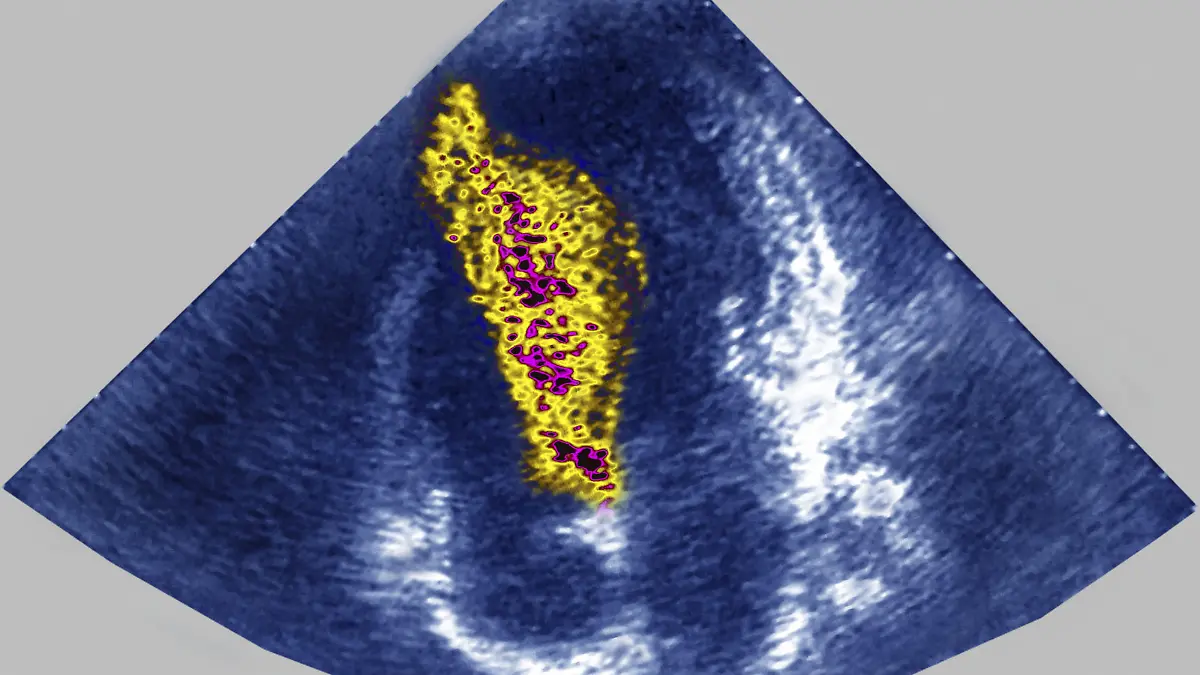

organischen Gewebewachstum nach Organbeeinträchtigungen, so beispielsweise die Größenzunahme einer Herzkammer, durch die das Herz bei Herzklappenfehler die Mehrbelastung auszugleichen versucht (ventrikuläre Hypertrophie).